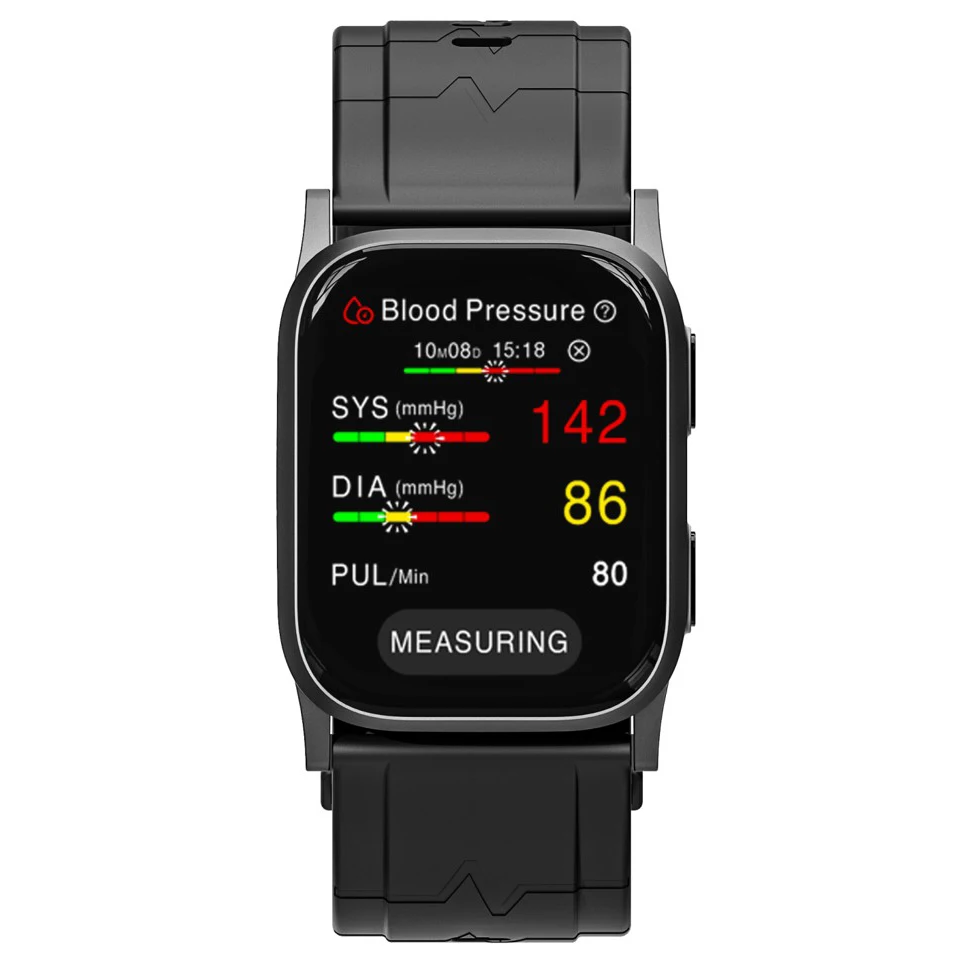

Application: Wrist

Bluetooth: Yes

Brand Name: komwell

Certification: CE

Choice: yes

Data Storage: Yes

Function: Blood pressure,ecg,Oximetry

Hign-concerned Chemical: None

Is Batteries Included: Yes

Item Type: blood pressure

Model Number: BPW1

Origin: China Mainland

System support: Bluetooth4.0 for iOS and Android

komwell Model: W1

languages: 17 languages can be freely converted

semi_Choice: yes

voice: Y